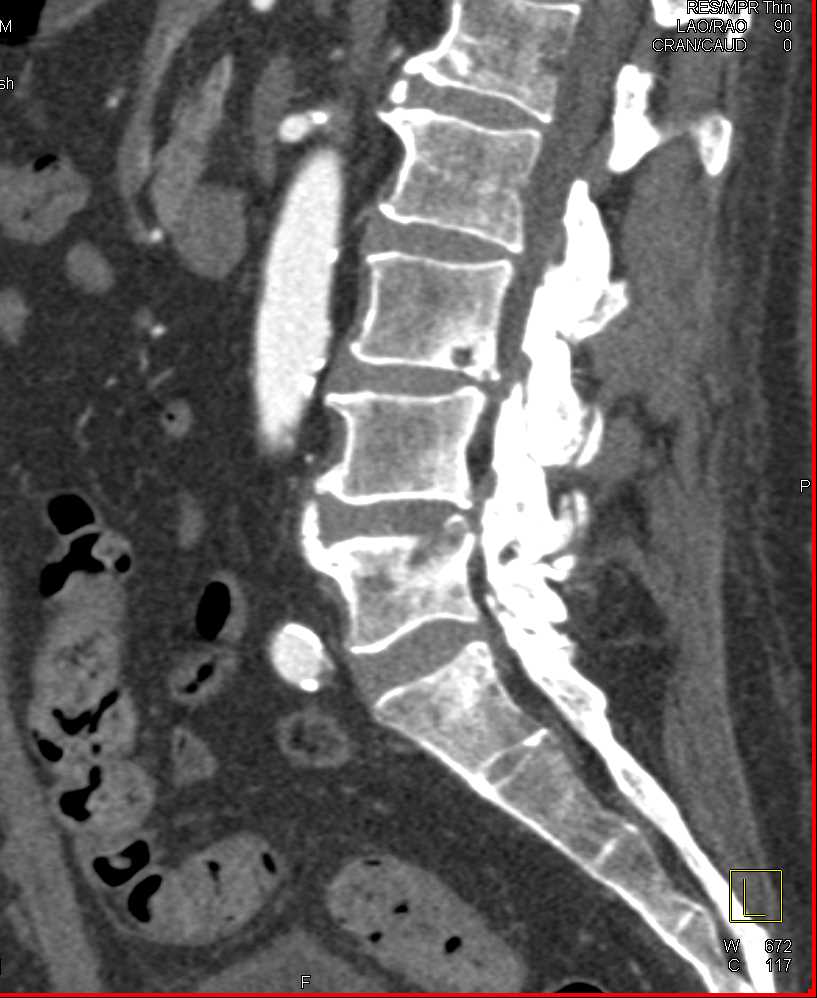

Infection at L4-L5 interspace